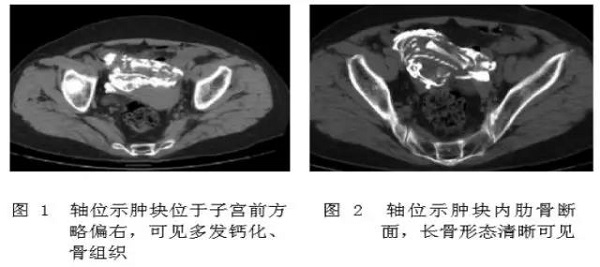

石胎的主要诊断手段是影像学检查,包括 B 超,X 线和 CT 等。超声下可见高回声光团和胎儿结构回声,X 线可以看到胎头、脊柱、肋骨及四肢等结构,CT 表现可见钙化的胎膜和胎儿(见下图)。

石胎 CT 图像

(图片来源:邓小强. 腹腔石胎 1 例. 中国医学影像技术 2010, 26( 11))

鉴别诊断有难度时,可以考虑进行多层螺旋 CT(MSCT)扫描,更能直观、多方位、多角度地显示脊柱、肋骨、四肢及胎膜钙化情况,为临床提供准确的影像信息(见下图)。

图片来源:吴德红等. MSCT 对腹腔石胎的诊断价值. CT 理论与应用研究, 2015, 24(1): 129-134.